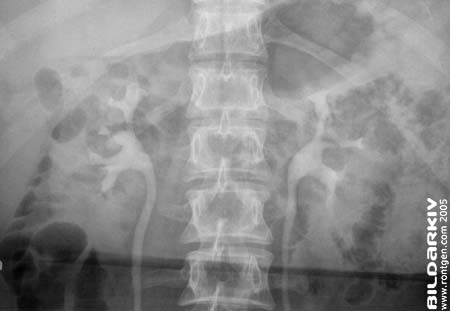

Urografi 6

Frontal bild båda njurarna 5 minuter efter kontrast injektion.